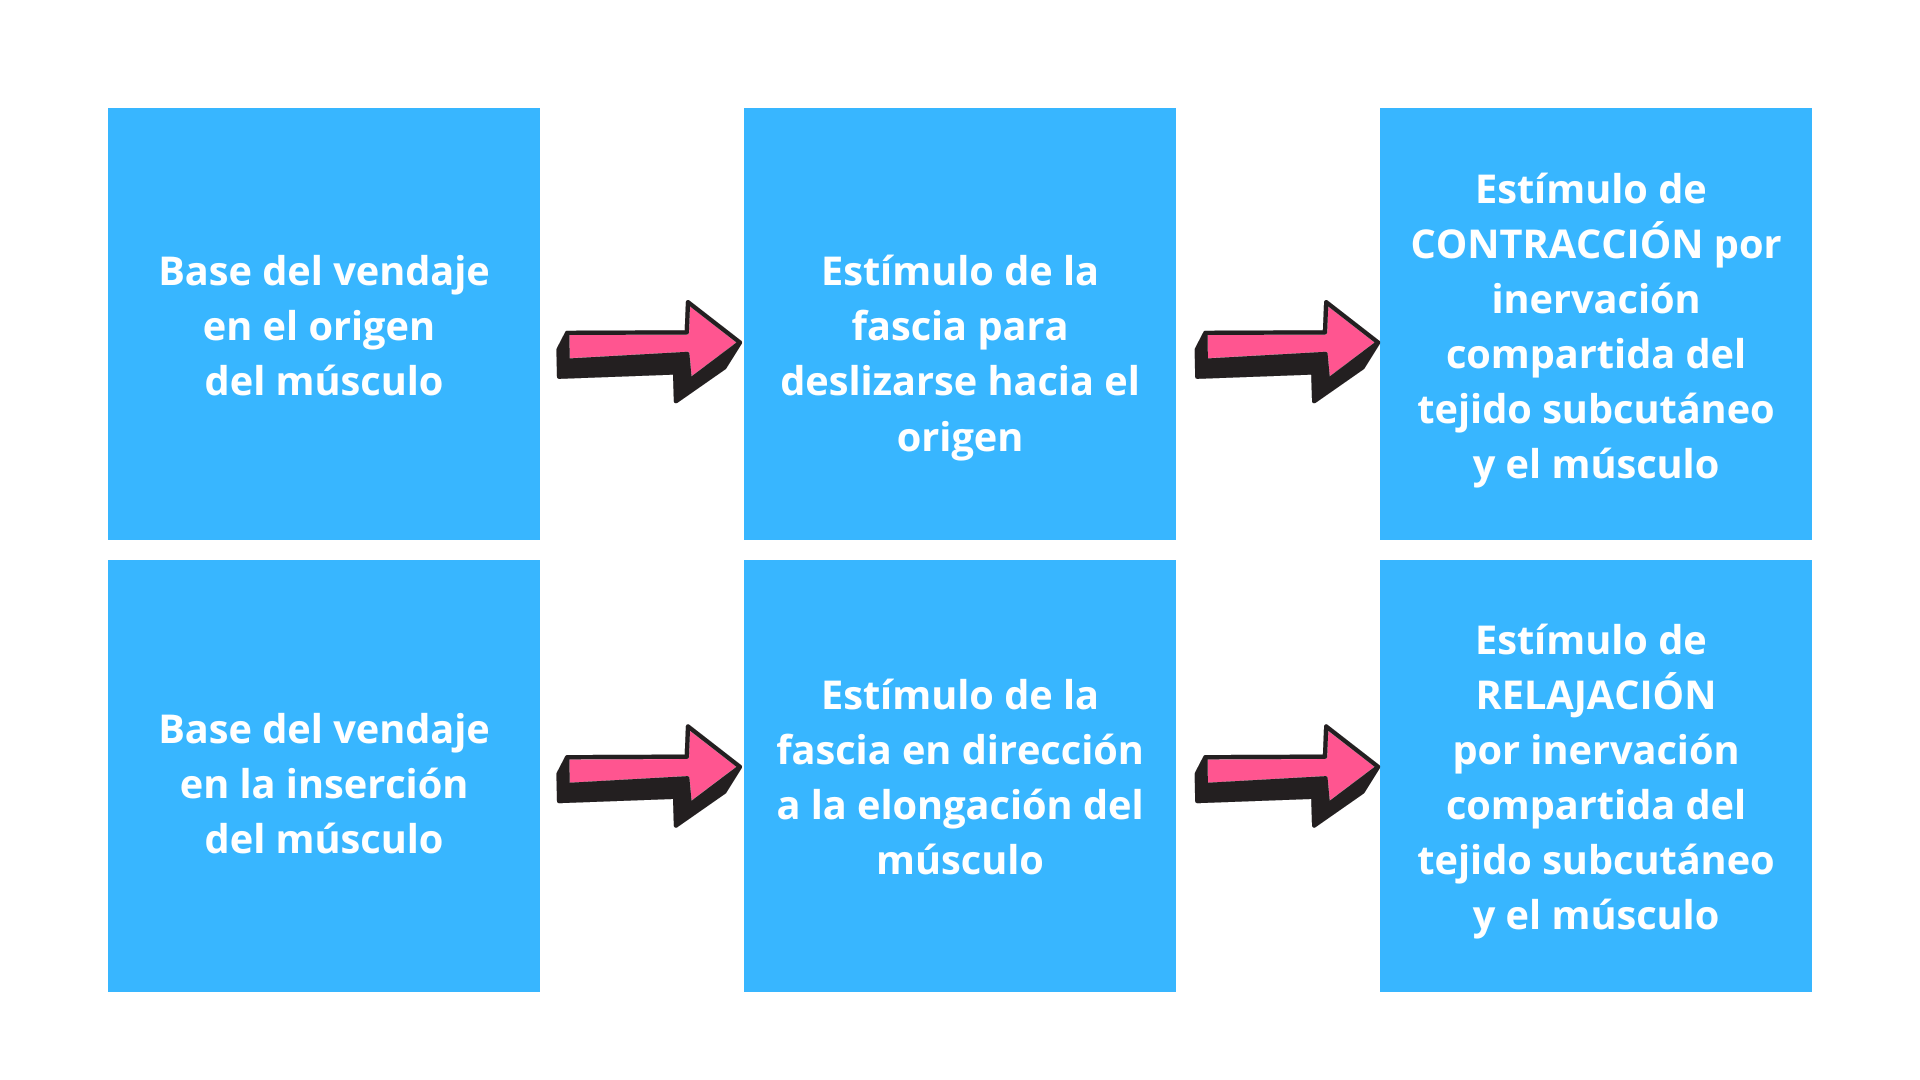

Hay que tener en cuenta que el tejido subcutáneo o fascia superficial comparte inervación con el músculo en la zona que limitan ambos con la fascia profunda, así que cuando se provoca un estímulo de deslizamiento entre el tejido subcutáneo y la fascia, estaremos provocando un estímulo sobre el músculo para contraerse o relajarse.

Las fibras elásticas del esparadrapo se retraen en dirección a la base, entendiendo por base el anclaje inicial del vendaje, por lo tanto, dependiendo de si la base se ubica en el punto móvil o fijo, del segmento a tratar, podemos generar tracción en un sentido o en el contrario, consiguiendo así relajar o contraer las fibras musculares.

Para acabar de entenderlo hemos de conocer dos conceptos más; PUNTO FIJO u ORIGEN y PUNTO MÓVIL o INSERCIÓN, por lo general tomamos como punto fijo el origen de un músculo y su inserción como punto móvil. Cuando se realiza una contracción muscular las fibras se desplazan en dirección al punto fijo u origen.

EN ESTE CUADRO VEMOS UN ESQUEMA DE LO QUE OCURRE: